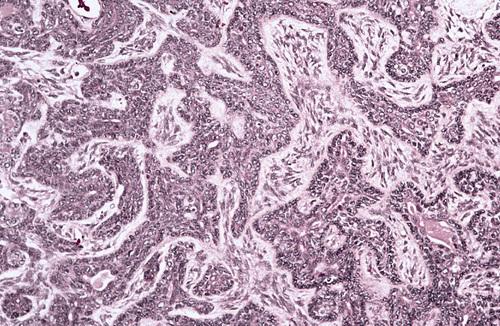

Low-power view of a moderately well-differentiated tumor showing ductal and cystic spaces surrounded by mucous and squamous (epidermoid) cells.

mucoepidermoid carcinoma

This low-grade tumor shows numerous large mucous cells surrounding a cystic space. Higher grade tumors show consist of solid islands of squamous and intermediate cells, demonstrating considerable pleomorphism and mitotic activity.

mucoepidermoid carcinoma

High-power view showing a sheet of squamous epidermoid cells with focal mucus-producing cells (left). A third type of cell—the intermediate cell— is believed to be a progenitor of both the mucous and the epidermoid cells.

mucoepidermoid carcinoma

Clear cell tumor. The typical presentation for this tumor is a mixture of mucus-producing cells and squamous (epidermoid) cells

mucoepidermoid carcinoma

High-power view showing a sheet of pleomorphic squamous epithelial cells intermixed with mucous and intermediate cells. Lower grade tumors show cyst formation, minimal cellular atypia, and a greater proportion of mucous cells.

mucoepidermoid carcinoma